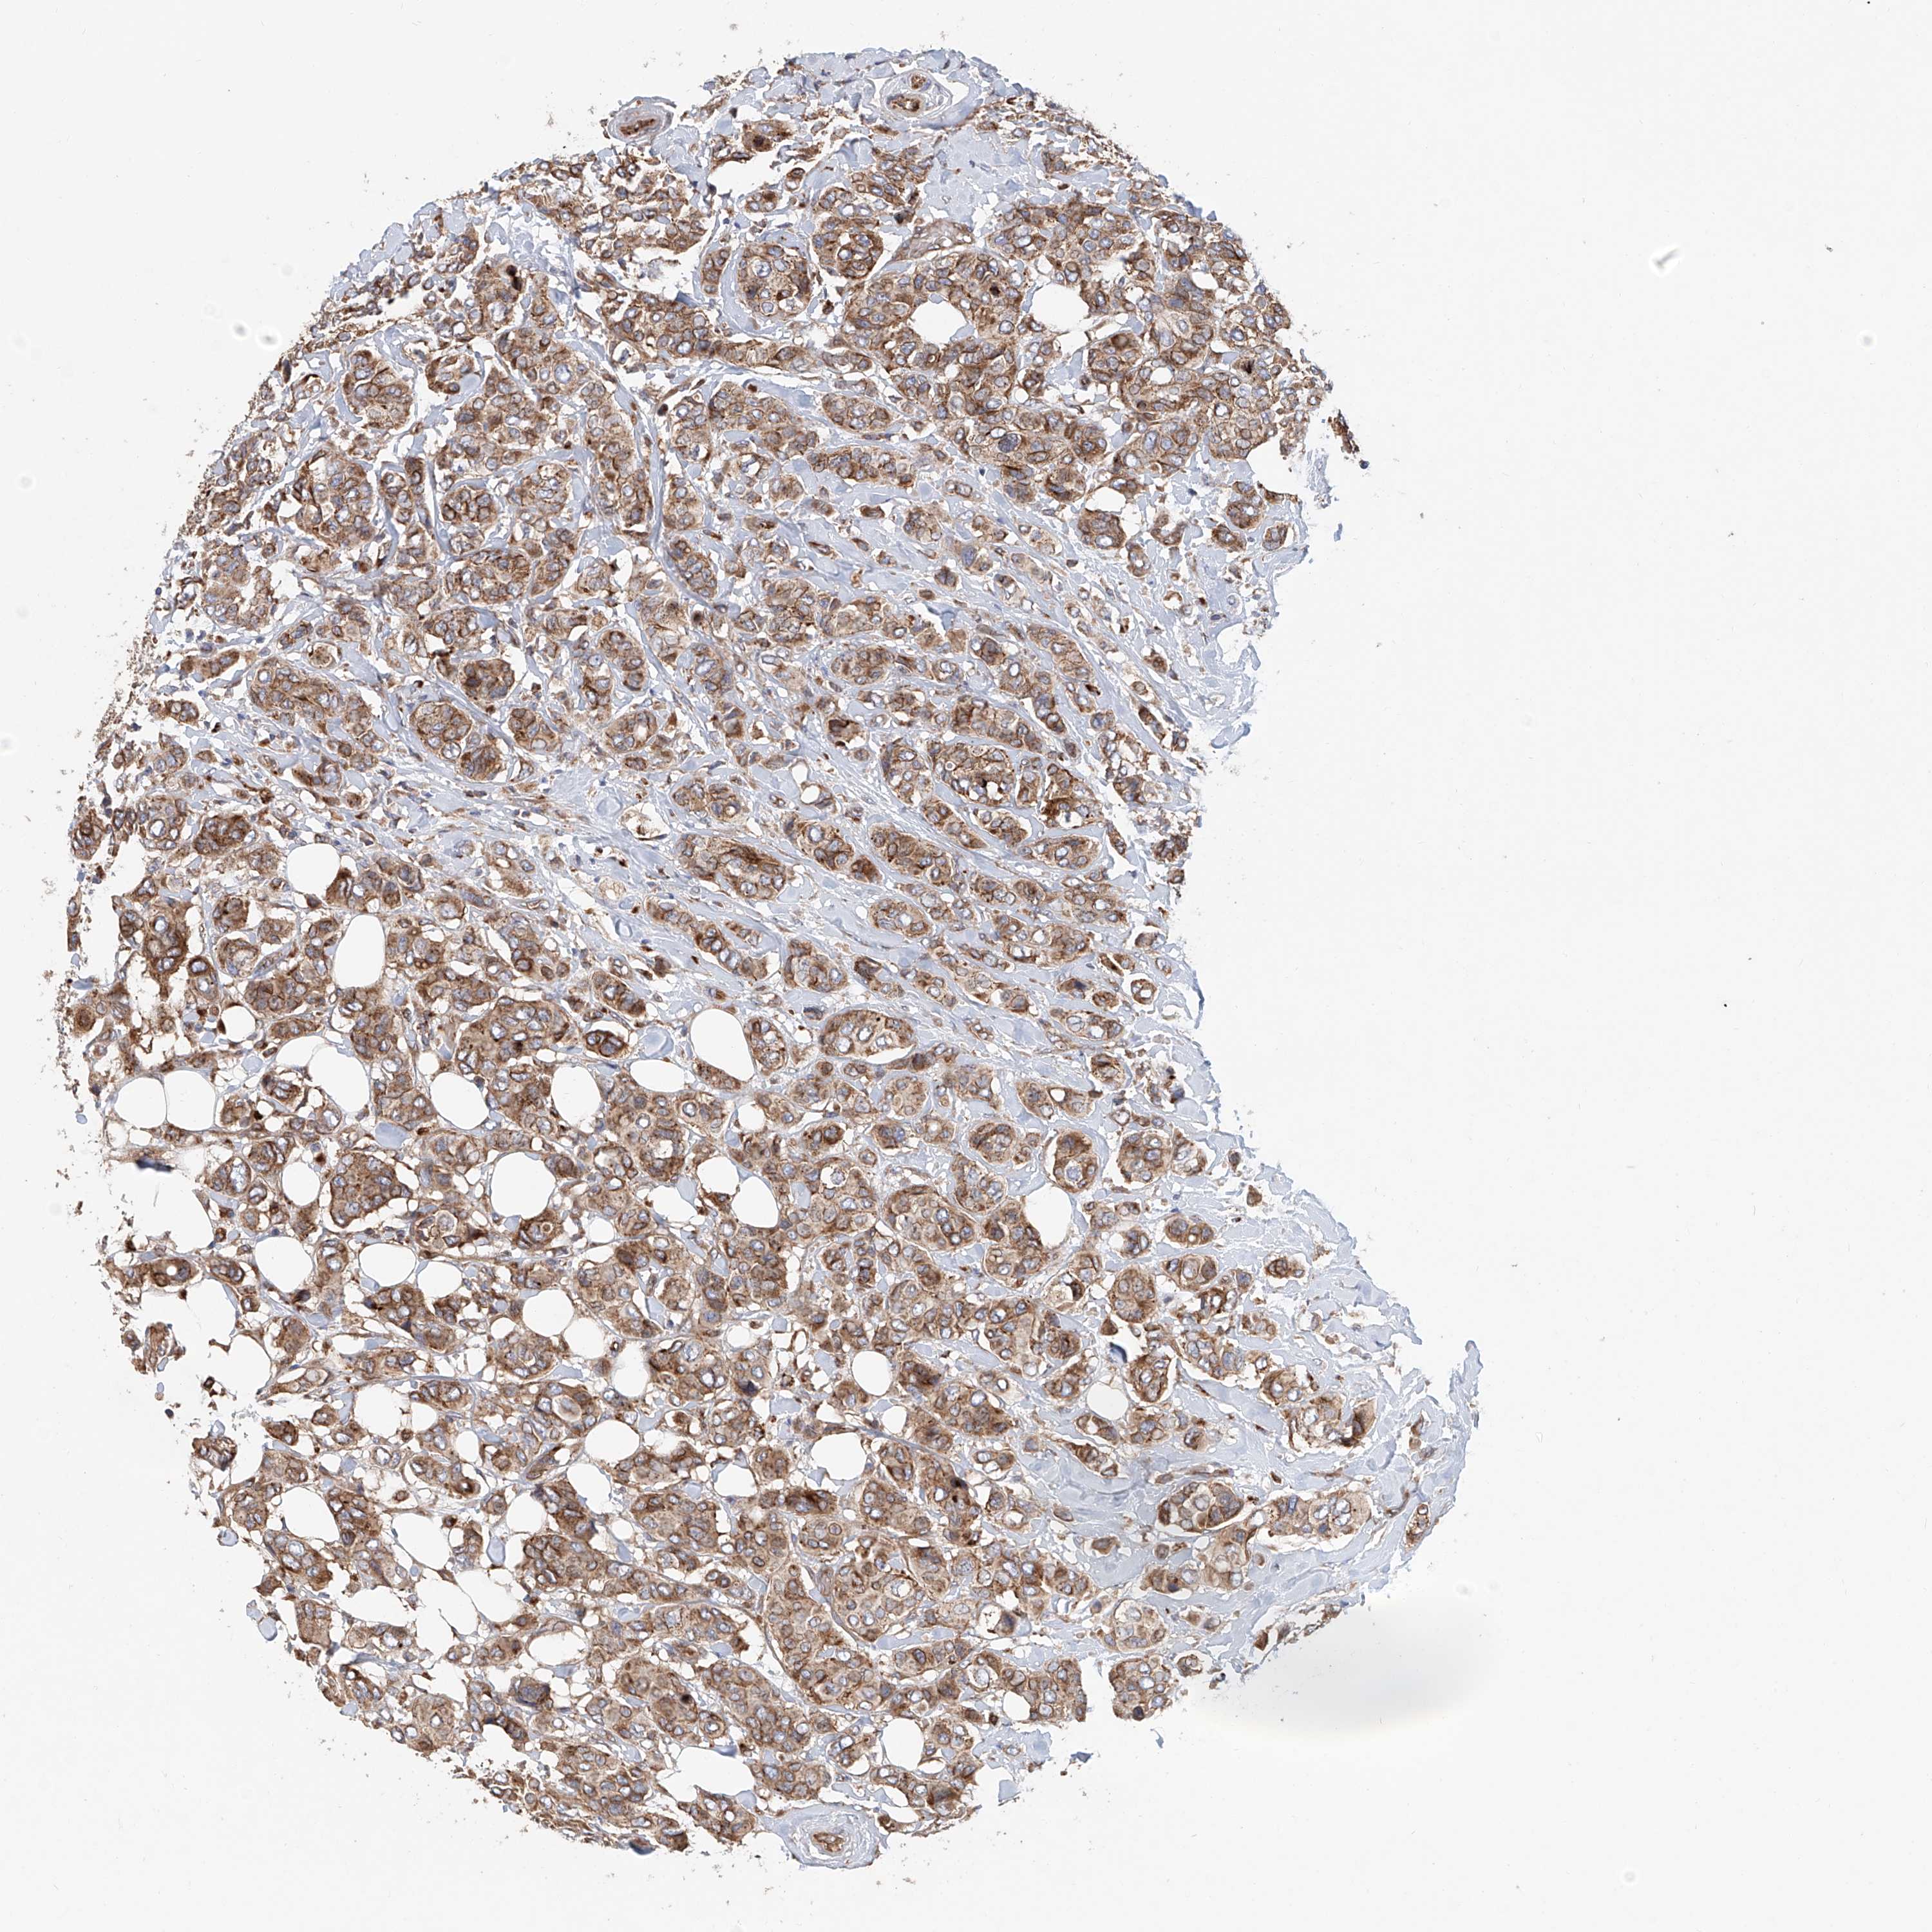

CANCER BREAST CANCER Show tissue menu

BRCA TCGA BRCA VALIDATION PROTEIN EXPRESSION